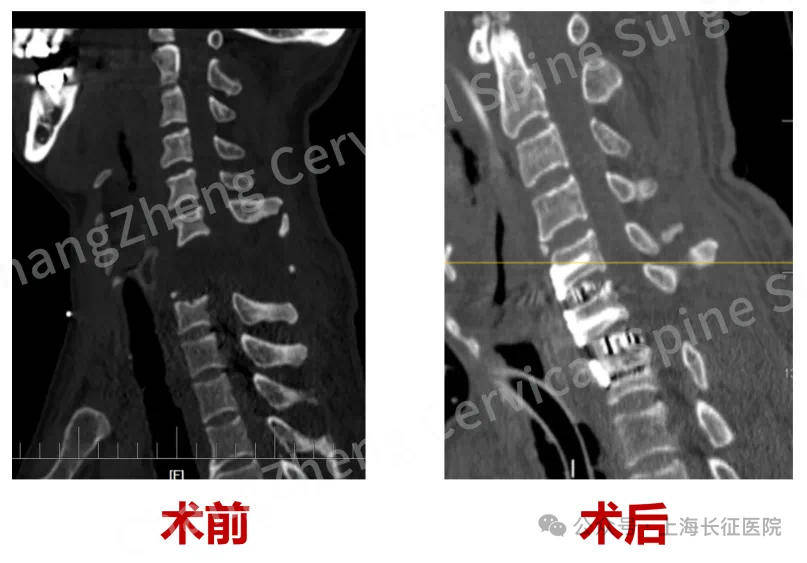

▲术前、术后影像对比 图据医院

据了解,“身首离断”式的颈椎大跨度脱位本就罕见,成功复位更是闻所未闻。术前影像学检查显示,患者脊髓严重挫伤、关键的神经血管结构撕裂。